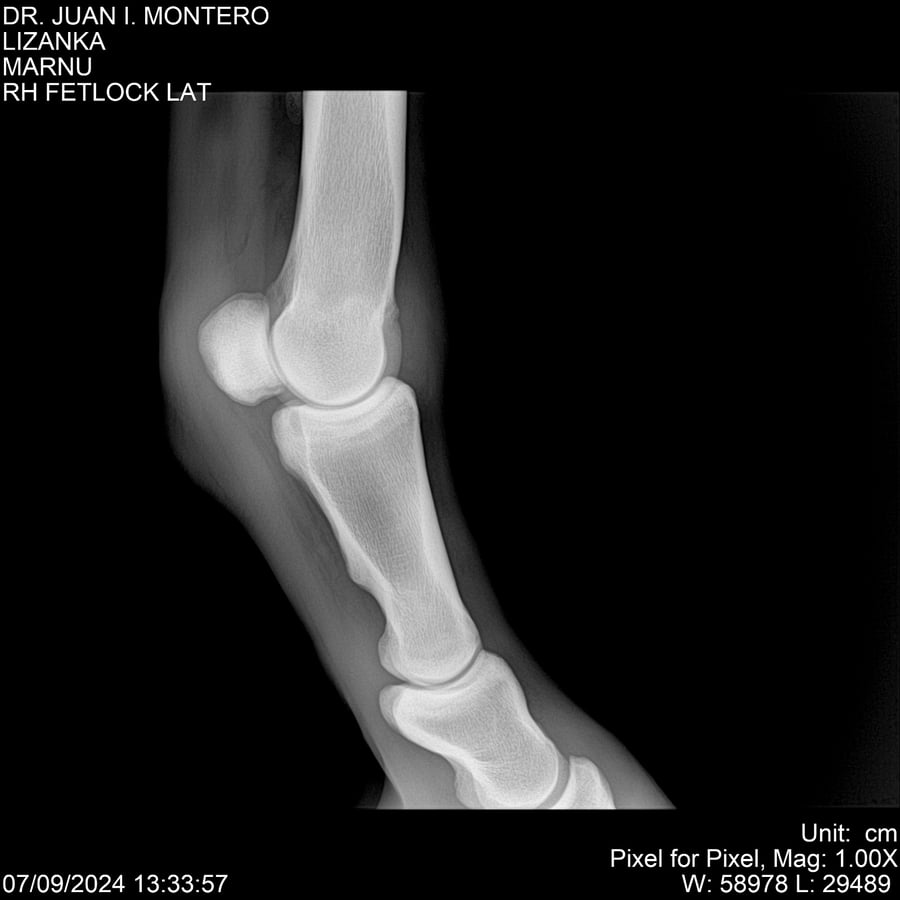

LOTE 18, LIZANKA Lote Anterior Volver al remate Lote Siguiente Ficha Contacto Montevideo - Ficha del Lote Identificador: #282512 Categoría: Yeguarizos Montevideo - 62 Visualizaciones ClicData Contacto Empresa: Abelenda N. R., Walter Hugo Nombre*: Teléfono* : E-mail* : Mensaje Enviar Registrese gratis Este contenido Exclusivo está disponible sólo para usuarios registrados Ingresar